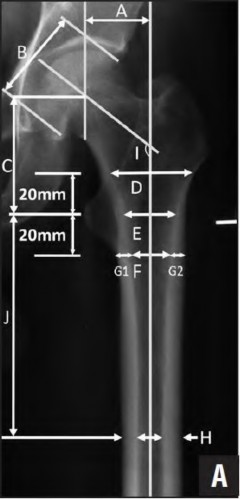

Illustration A depicts the Vancouver classification for perioperative periprosthetic femur fractures. Type A involves the proximal metaphysis [labelled A-C], type B involves the diaphysis [D-F]and type C fractures are distal to the stem tip and not amenable to insertion of the longest revision stem [G]. Each type is further sub-classified into type I if there is only a cortical perforation, type 2 is there is a nondisplaced crack and type 3 is there is a displaced unstable fracture pattern. Illustration B is an image from Zhao et al demonstrating radiographic measurements. The MDI is calculated by (D/F) / (G1+G2) where D = canal width 20mm above the mid-lesser trochanter line, F

= canal width 20mm below the mid-lesser trochanter line, G1 and G2 = two

cortical thicknesses at the same level as line F.